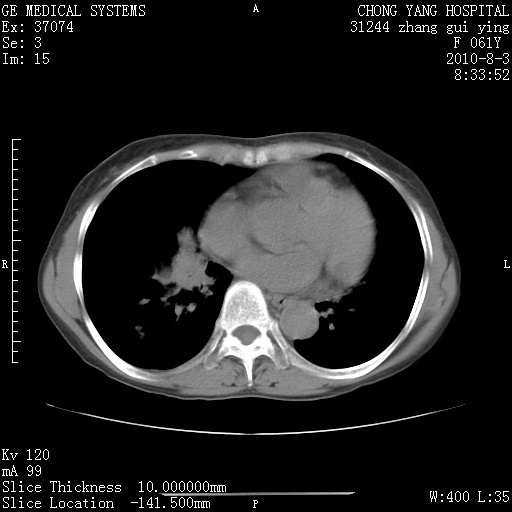

标题: CT28314:F61Y胸部增强,发热咳嗽一周入院,后面的为一周前平

1、支持考虑右侧中央型肺癌伴右肺中叶节段性不张及下叶支气管黏液痰栓    2、左肺上叶舌段感染。

双肺感染性病变,不除外合并结核感染。

确切的说:1:右肺下叶中心型肺癌侵及中叶支气管并中叶不张,纵膈淋巴结转移。2:左肺舌叶炎症。3:右侧胸腔少量积液

1:右肺下叶中心型肺癌侵及中叶支气管并中叶不张,纵膈淋巴结转移。2:左肺舌叶炎症。3:右侧胸腔少量积液。支持!

右肺下叶内基底段近膈不规则肿块,考虑右肺下叶周围型肺癌可能性大。